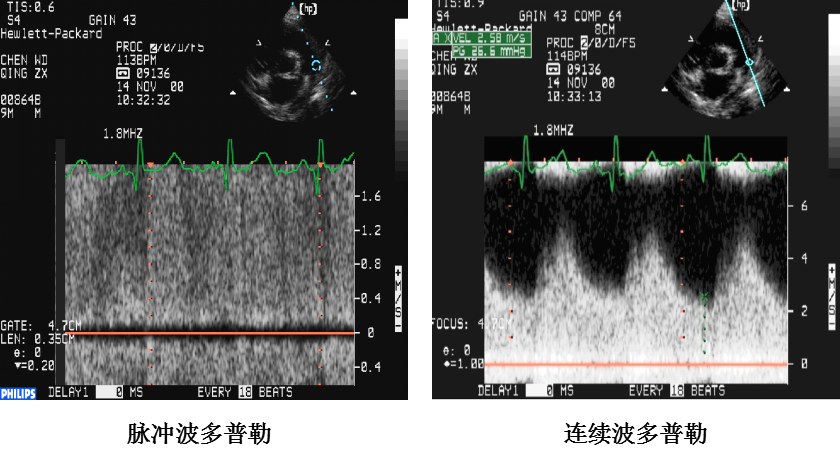

动脉导管未闭:超声心动图表现